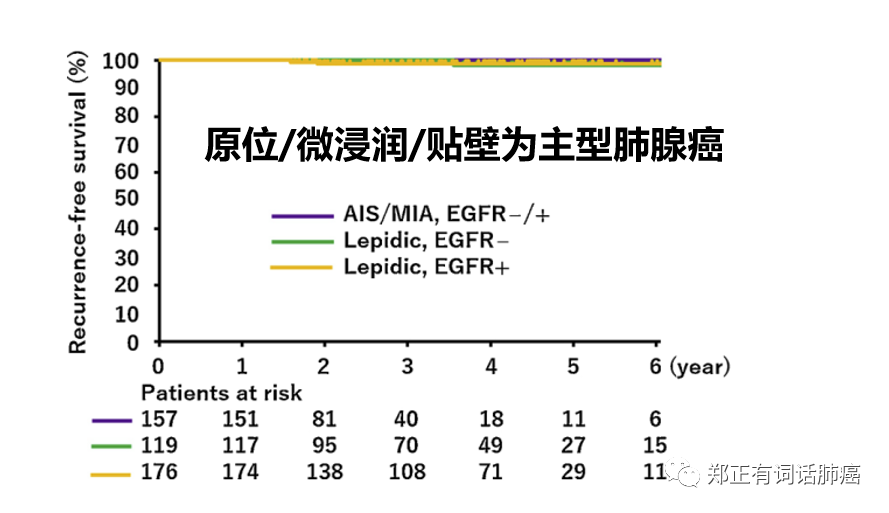

在低度恶性的原位/微浸润/贴壁为主型肺腺癌中,是否携带EGFR驱动基因突变不会对预后产生显著影响。

而在乳头/腺泡为主的中度侵袭和实体/微乳头为主的高度侵袭性群体,携带EGFR驱动患者均表现出更快的复发情况,其中,高度侵袭性者更甚。